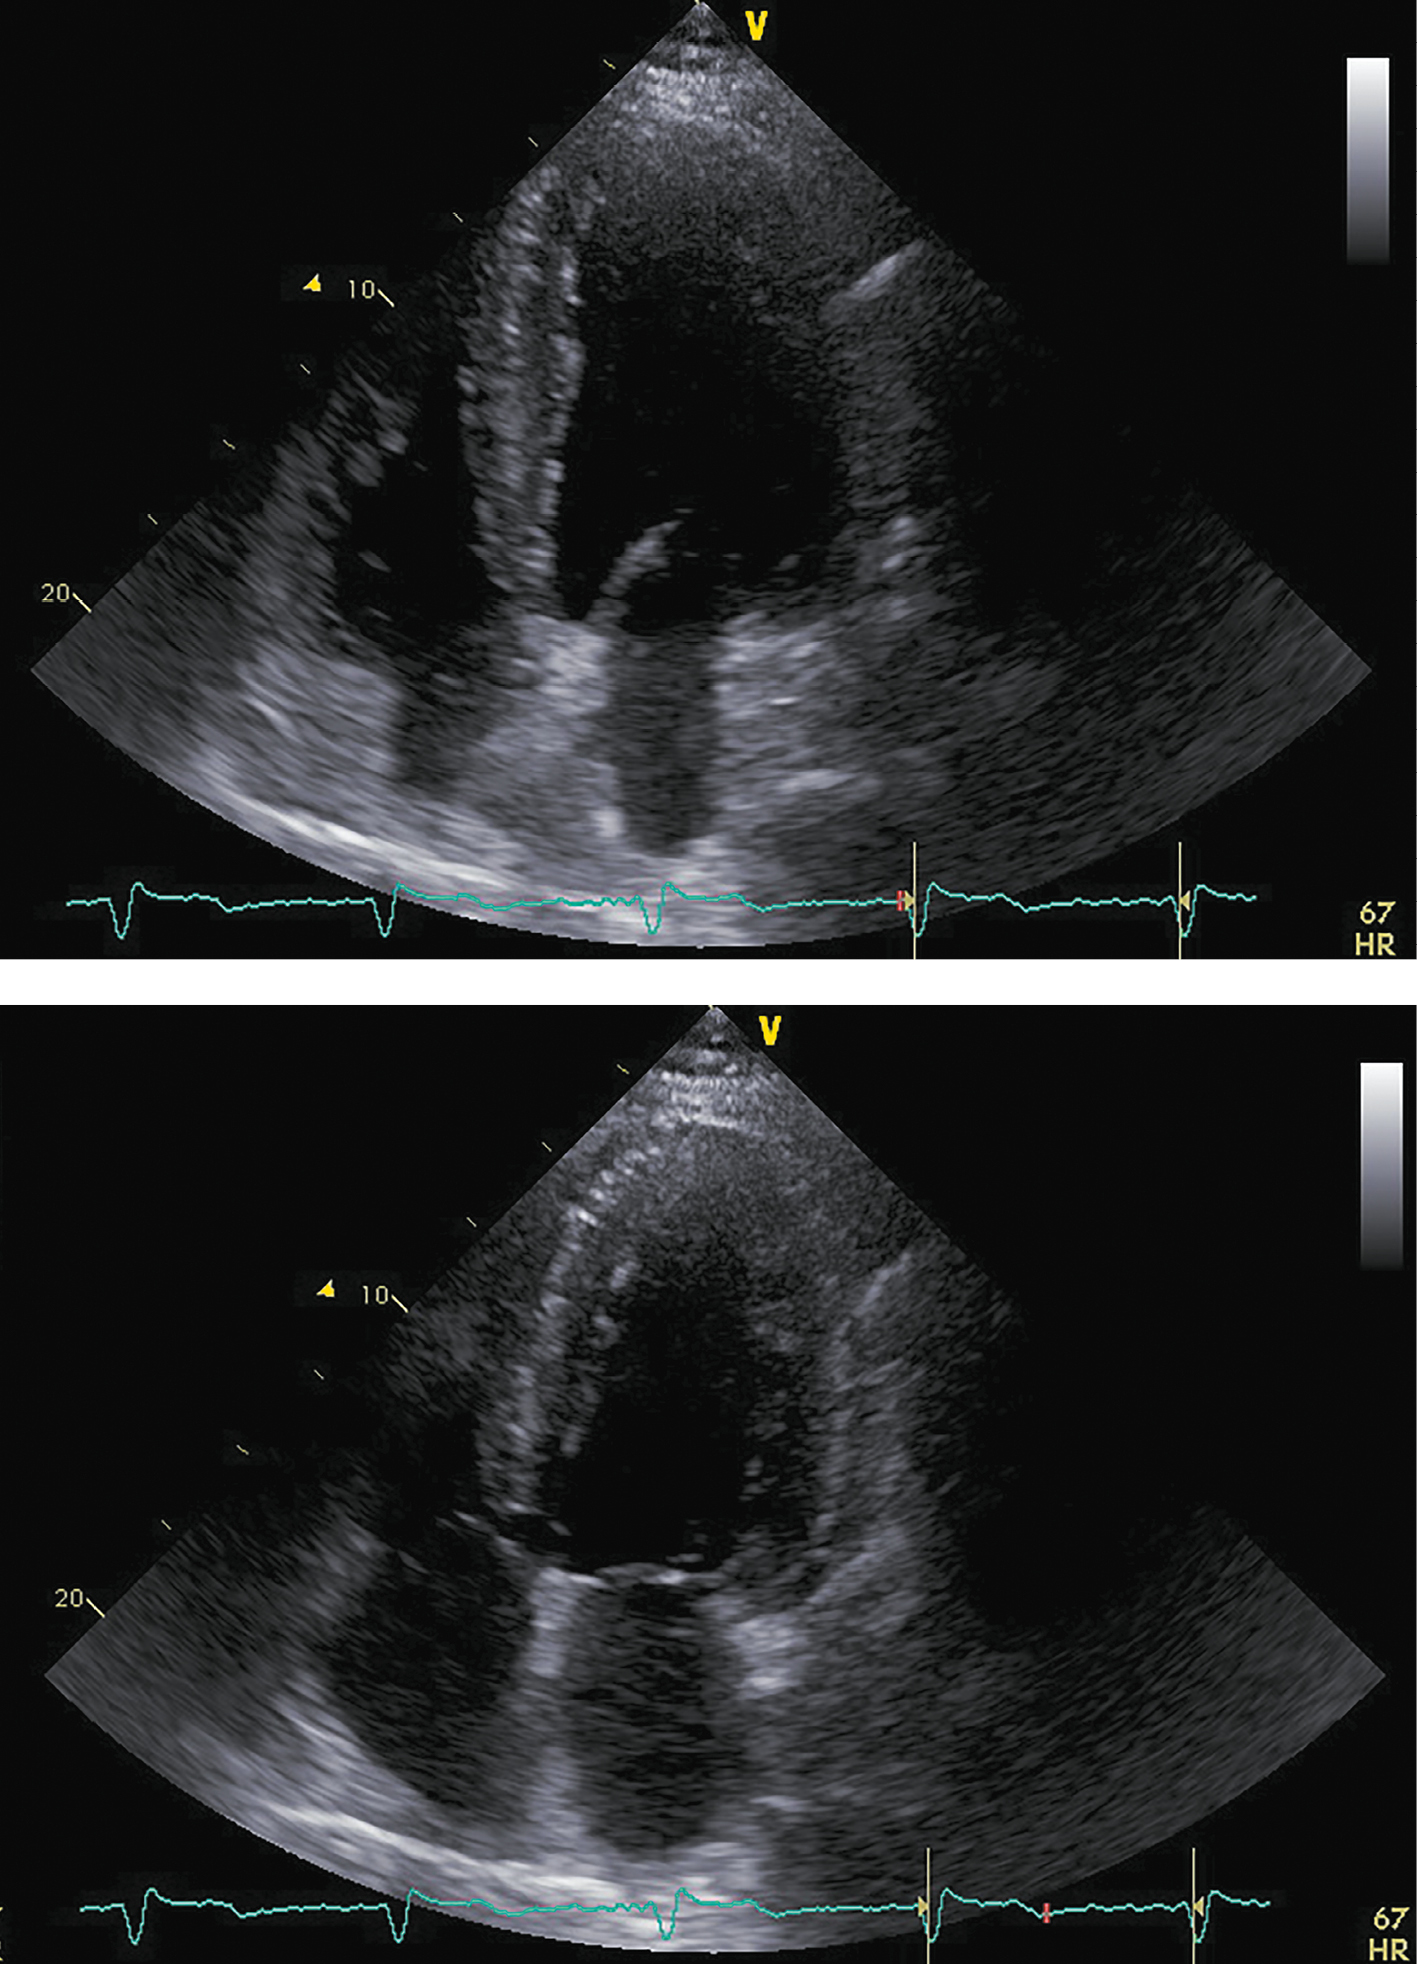

В ноябре 2017 г. пациент госпитализирован повторно для проведения нейрохирургического лечения. Пациент указал, что принимал предписанную терапию в полном объеме. Каких-либо нежелательных лекарственных реакций не выявлено. На фоне лечения симптомы ХСН заметно регрессировали, толерантность к физическим нагрузкам возросла до уровня II ф.к. по NYHA. Физикальной симптоматики легочного застоя и увеличения печени не отмечалось. При контрольной ЭХОКГ (рис. 5; табл. 3) выявлены уменьшение размеров и объемов левого желудочка, значительное увеличение ФВ ЛЖ (до 43%) и снижение класса диастолической дисфункции ЛЖ.

Рисунок 5. ЭХОКГ перед аденомэктомией.

Примечание: верхушечная 4-камерная позиция (сверху представлен кадр в диастолу, снизу — в систолу).

Таблица 3. ЭХОКГ-показатели перед аденомэктомией

|

Показатель |

Значение/индекс |

Объем левого предсердия |

100 мл/54 мл/м² |

Передне-задний размер левого желудочка |

7,20 см/2,89 см/м² |

Конечно-диастолический объем левого желудочка |

285 мл/117 мл/м² |

Конечно-систолический объем левого желудочка |

162 мл/67 мл/м² |

Локальная кинетика левого желудочка |

умеренный диффузный гипокинез |

Фракция выброса левого желудочка (усреднение по 4- и 2-камерным верхушечным позициям) |

43% |

Диастолическая функция левого желудочка |

градация II, псевдо-нормальный тип |

Конечно-диастолическая площадь правого желудочка |

25,0 см²/10,0 см²/м² |

Конечно-систолическая площадь правого желудочка |

12,0 см²/4,8 см/м² |

Фракция систолического уменьшения площади |

52% |

Расчетное систолическое давление в легочной артерии |

43 мм рт.ст. |